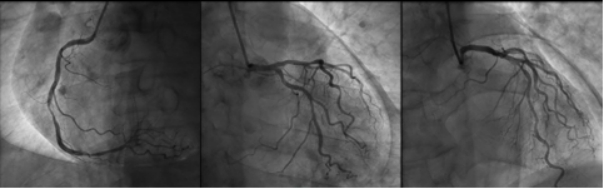

| 图 3 冠脉造影提示冠脉轻至重度狭窄,心影周围可见弧形透亮带 |

1 资料与方法患者男性,70岁,因“胸闷3 d,加重伴呼吸困难1 d”于2019年9月13日入外院。患者3 d前无明显诱因出现胸闷,伴全身乏力,夜间睡眠差(可平卧),初未予重视,1 d前胸闷加重,伴呼吸困难、运动耐量明显下降、大汗淋漓、皮肤湿冷,至外院就诊,查心电图(图 1):交界性逸搏,肢体导联低电压,Ⅰ、Ⅱ、Ⅲ、aVF、V4、V5、V6导联ST段抬高0.15 mV~0.4 mV,aVR、aVL、V1导联ST段压低0.05 mV~0.2 mV,aVL、V1导联T波倒置;心肌酶:CKMB 27.1 U/L,NT-proBNP 3 298 pg/mL。外院考虑不排除急性心肌梗死导致的心源性休克,经口气管插管接呼吸机辅助通气后为进一步诊治转入本院。患者家属否认患者有外科手术、外伤、气胸及哮喘发作史,起病以来无畏寒、高热,大、小便正常,既往1年余前因“反复咳嗽伴咳血丝痰”在外院诊断为右肺门鳞癌,合并高血压病、2型糖尿病,经依托泊苷+顺铂化疗,具体剂量不详。2019-09-07复查胸部CT提示右肺病灶较前缩小。体格检查:体温35ºC,血压86/43 mmHg,心率53次/min,呼吸15次/min(经口气管插管呼吸机辅助呼吸),神志昏迷,双侧颈静脉怒张,气管居中,桶状胸,胸廓对称,双肺呼吸动度对称,叩诊呈清音,听诊呼吸音清,双肺未闻及干湿性啰音,心前区无隆起,叩诊心界消失,心音低弱遥远,桡动脉、股动脉搏动可触及。入院后复查心电图(图 2):心房颤动,肢体导联及胸导联低电压,各导联ST-T改变较前相似,未见明显动态演变。血常规:白细胞1.27×109/L,中性粒细胞1.15×109/L,血红蛋白98 g/L,降钙素原43.01 ng/mL,超敏肌钙蛋白Ⅰ 0.048 ng/mL。急诊冠脉造影(图 3):左前降支近段轻度狭窄,中段心肌桥,收缩期重度狭窄,左回旋支远段中度狭窄,右冠中段重度狭窄,TIMI血流均为3级。患者超敏肌钙蛋白I未见明显升高,冠脉血流通畅,排除急性心肌梗死引起的ST段抬高。心脏彩超:气体干扰较大,仅能从剑突下观察,心包腔内未见积液。胸片(图 4):纵隔内可见条状透亮带,心影周围可见一弧形透亮带,考虑心包积气、纵隔气肿。入院诊断为“①心包积气、②纵隔气肿、③右肺鳞癌”,经剑突下途径行心包穿刺置管术+闭式引流术,术后液封瓶内见气体逸出,患者血压较前逐渐上升。完善胸部CT(图 5):右侧肺门增大,右主支气管与上叶支气管壁交界处见小缺损,考虑支气管破裂,心包、纵隔、胸腔及腹腔积气。纤维支气管镜(图 6)检查:可见右主支气管距隆突约1 cm处见破损,破损处周围组织呈白色,不排除癌组织浸润可能。病因考虑为右肺门鳞癌浸润右主支气管,穿孔后经纵隔与心包腔形成瘘道,引起心包积气。经过上述治疗后患者血流动力学稳定。

该例患者主要临床症状为胸闷伴有呼吸困难,体格检查时患者存在血流动力学不稳定及意识障碍,结合心电图、心肌酶结果,考虑急性心肌梗死导致心源性休克的可能,行急诊冠脉造影发现患者冠脉血流通畅,排除急性心肌梗死,同时在冠脉造影过程中发现患者心影周围存在弧形透亮带,转入ICU后行胸片检查证实心包积气的诊断。心包积气产生的原因主要为医源性操作(如心包穿刺术、胸腔穿刺术、射频消融术及埋入式起搏器植入术等)、心包炎、心包与邻近含气器官之间的瘘管形成以及外伤,其中正压通气亦是原因之一[9-12]。正压通气可迅速增加心包积气容积及加快其增长速度,从而加重心包填塞。该患者入外院后行经口气管插管接有创呼吸机辅助呼吸,本院胸部CT与支气管镜检查可见右主支气管破口,破损处周围组织呈白色,不排除癌组织浸润可能,考虑为右肺门鳞癌浸润右主支气管,穿孔后经瘘道与纵隔及心包腔相连,引起心包积气。